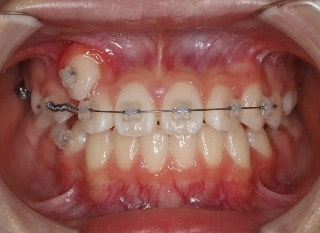

前歯装置装着時